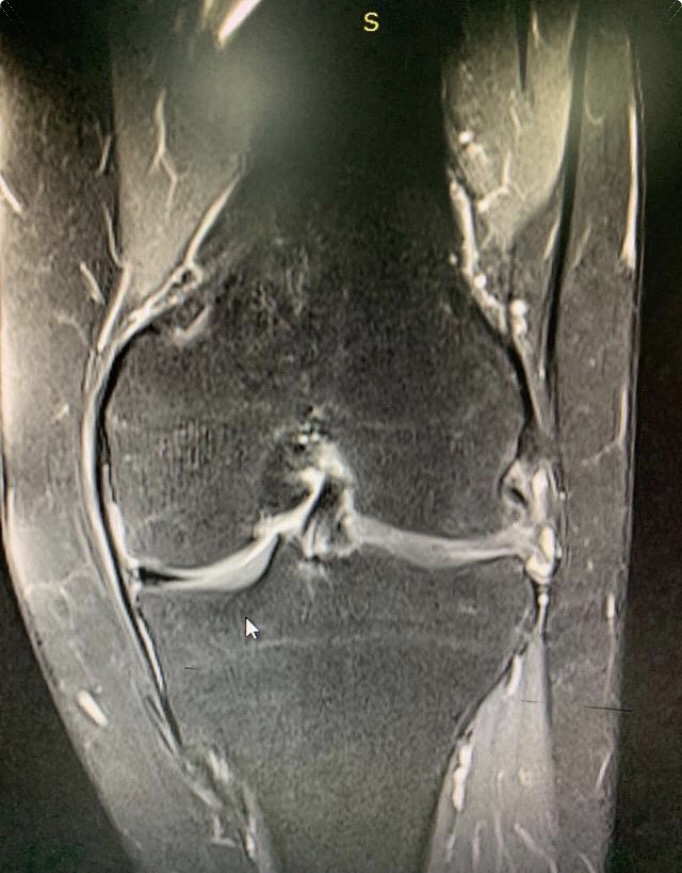

核磁共振显示的半月板损伤